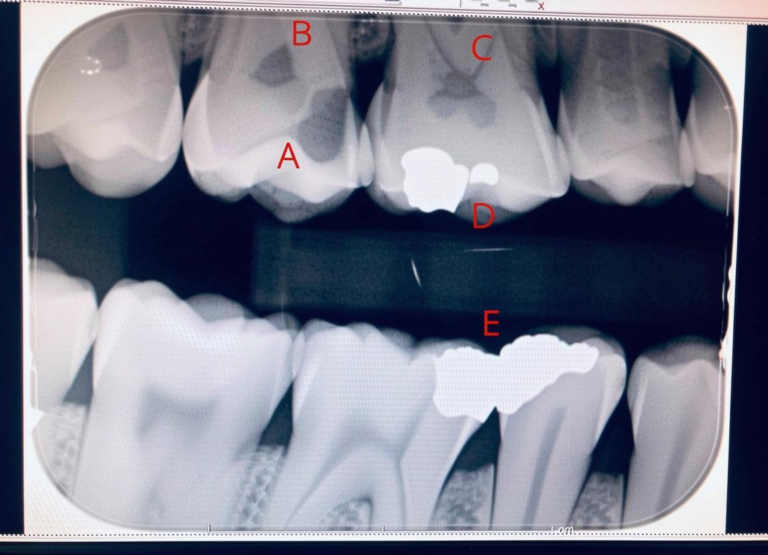

In the realm of dental health, cavities are often likened to whispered secrets—subtle indications of decay that…

The term “mod” in dentistry carries significance that extends beyond its conventional usage. It is often an…